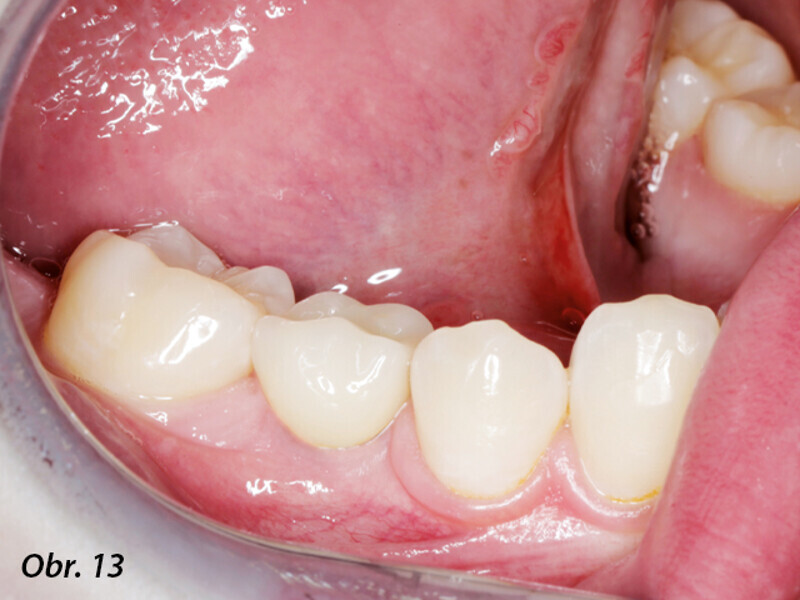

Řízená implantologie za použití řešení Planmeca all-in-one